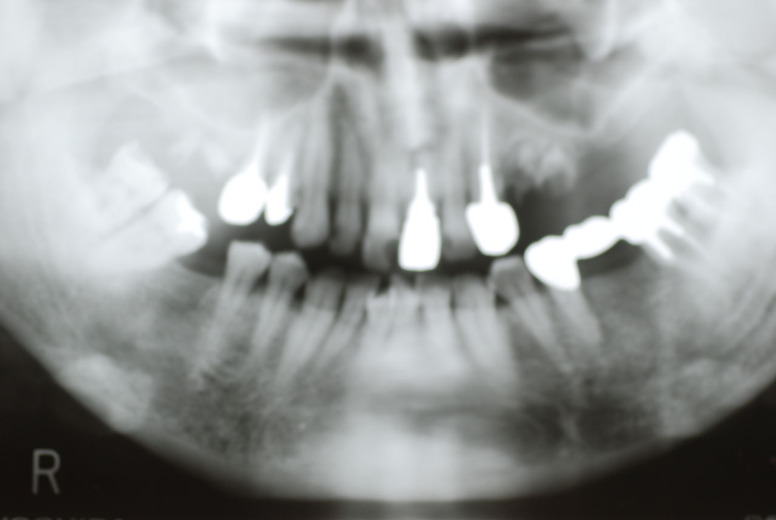

レントゲンでは小さいですが、こう言う虫歯が一番怖いのです。

隣の14歳大臼歯がひどい虫歯になり治療不可能になりつつある状態のレントゲン